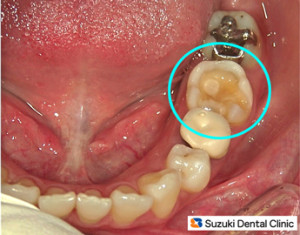

コラム「白い詰め物が割れた」の画像